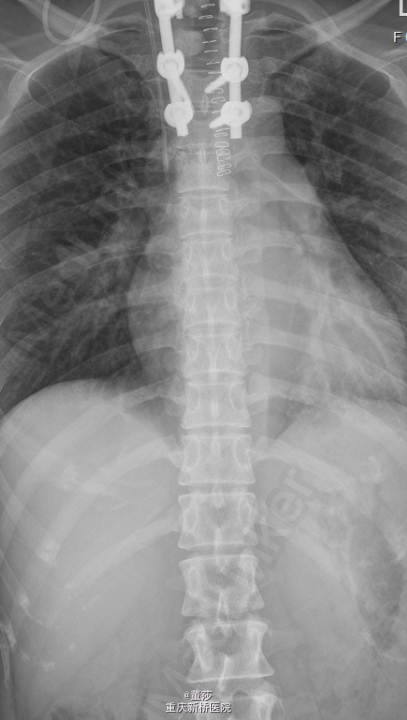

初步诊断:1.胸椎肿瘤:转移癌/肺恶性肿瘤。全身麻醉下行“胸椎恶性肿瘤后路肿瘤切除,椎管减压、内固定术”,术中予椎体内填充骨水泥,C5,C6,C7各打入一枚颈椎侧块螺钉,T3、T4两侧各打入一枚椎弓根螺钉,C臂机透视提示螺钉位置可。

术中冰冻:胸1,2椎肿瘤(2):显著增生的纤维结缔组织内有少量异型细胞,考虑转移性低分化腺癌。术后予锋替新2.0g ivgtt bid预防感染及镇痛,补液改善循环,促进愈合治疗等对症治疗。术后复查胸椎片:颈、胸椎后路术改变,术后内固定在位,胸1、2椎体内见高密度影。胸椎顺列。所见椎间隙无殊。